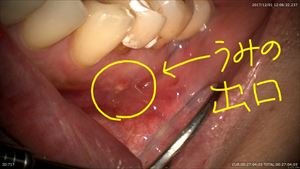

こんにちは。院長の武川です。本日も1日マイクロスコープ治療で歯の保存を行いました。充実した1日でした。今日は母親の治療。大宮から来てもらいました。母親は歯周病のリスクが高くメンテナンスを行ってきていましたが、右上の歯茎に何かできものができたと来院されました。

根の先に膿!!診断は「根尖性歯周炎」